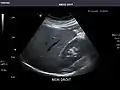

Spleen